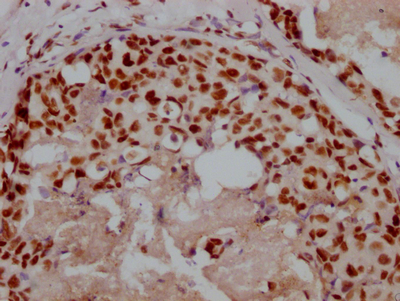

圖片: